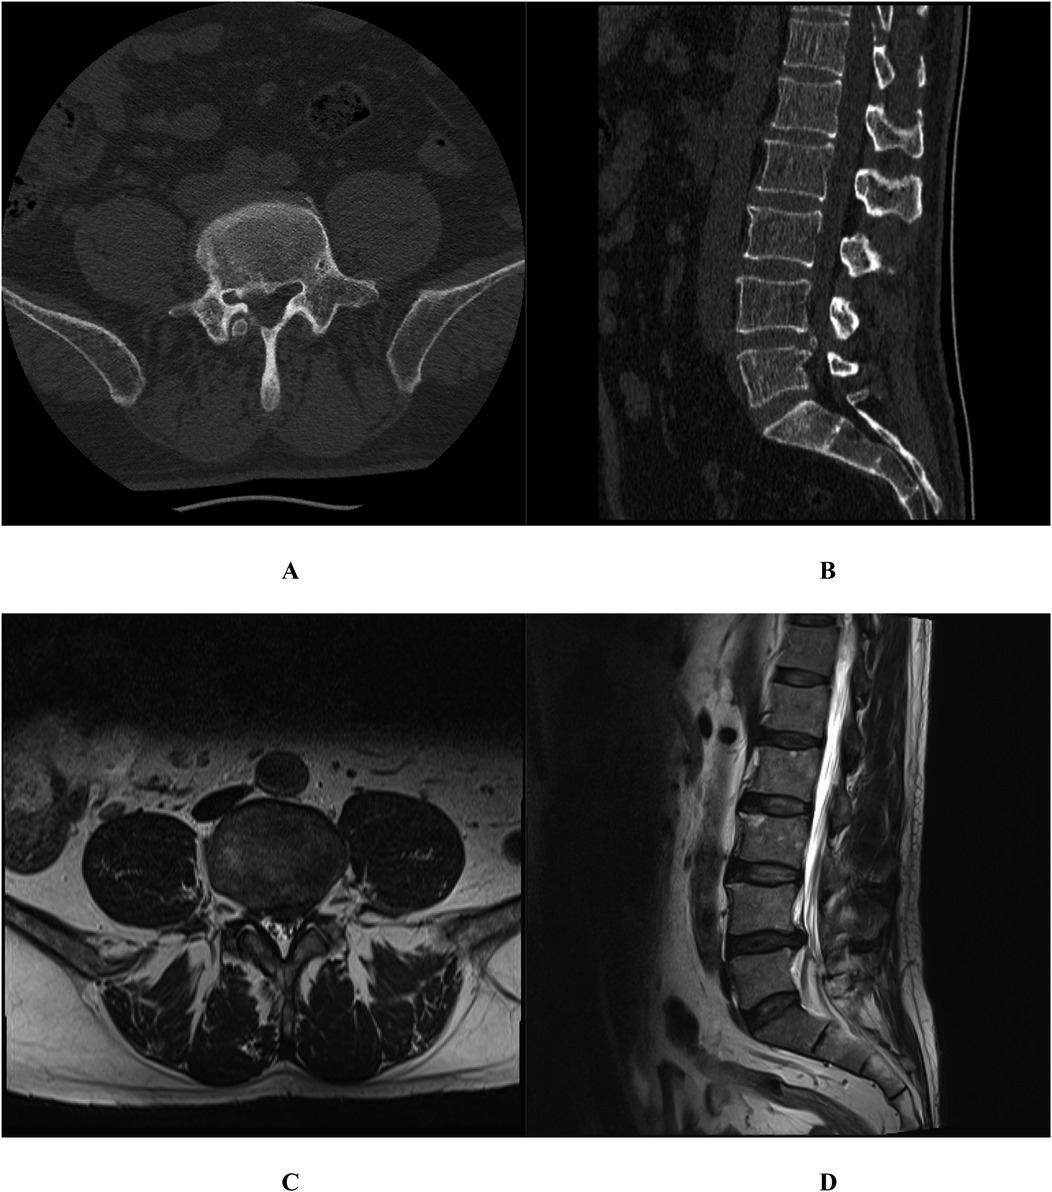

Posterior marginal osteophytes at the vertebral level are frequently observed in individuals with lumbar disc herniation (LDH); however, complete encasement of the nerve root by such osteophytes is exceedingly uncommon. We present two cases of surgical management of vertebral posterior marginal osteophytes completely encasing the nerve root. This report examined two cases of LDH accompanied by vertebral posterior marginal osteophytes completely encasing the nerve roots. Both patients underwent spinal canal decompression, discectomy, and intervertebral fusion. Postoperatively, varying degrees of nerve root injury were noted. By the 3-month follow-up, marked recovery in neurological function was achieved in both cases. The presence of vertebral posterior marginal osteophytes completely encasing the nerve root represents a notable risk factor for nerve root injury in LDH cases. Tailored surgical approaches are imperative to minimize complications and optimize patient outcomes.